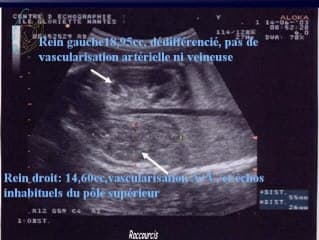

L'auteur est habitué à sortir des sentiers battus avec des sujets atyoiques pour nous faire sortir de notre routine. Ici il s'agit d'une analyse sur des reins trop petits au sein de l'acronyme CAKUT. Il présente des informations peu connues et des astuces telles que la longueur du rein atteint le nombre de semaines d'aménorrhée X 1,1. Ilmontre également l'importance de la génétique et des possibles syndromes dans ces hypodysplasies, ainsi que les facteurs maternels surtout l'étiologie toxique médicamenteuse ou alcoolique.